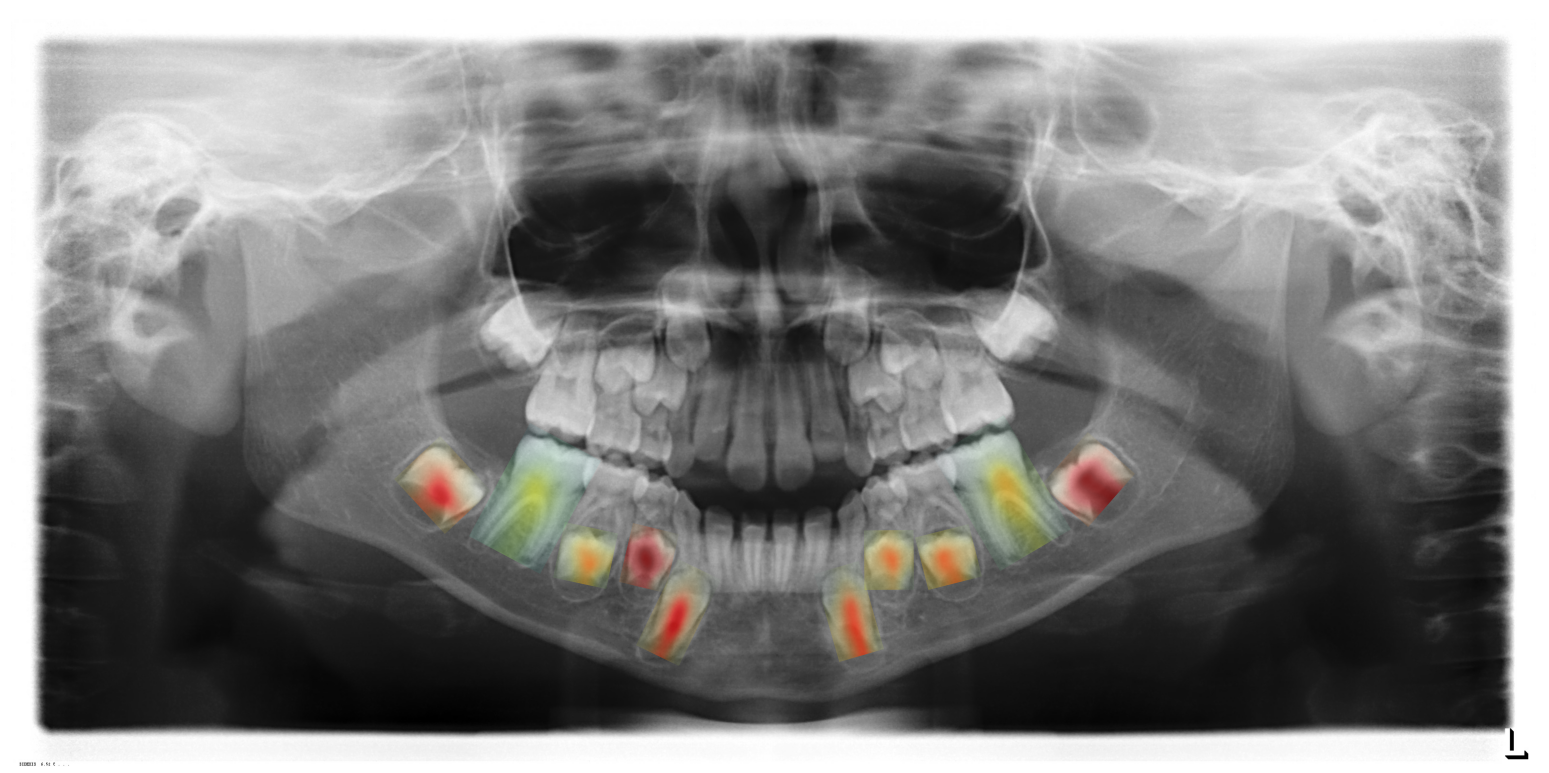

The heat-map of this patient is shown in Figure 5. Original Spanish texts are available on A.

Refer to caption

Figure 5: Example of a heat-map created from the OPG of a patient. In the image, the patient’s permanent mandibular teeth are highlighted. The most predictive teeth are marked in red, while the least predictive ones are in green. The uncolored lower teeth are primary (baby) teeth